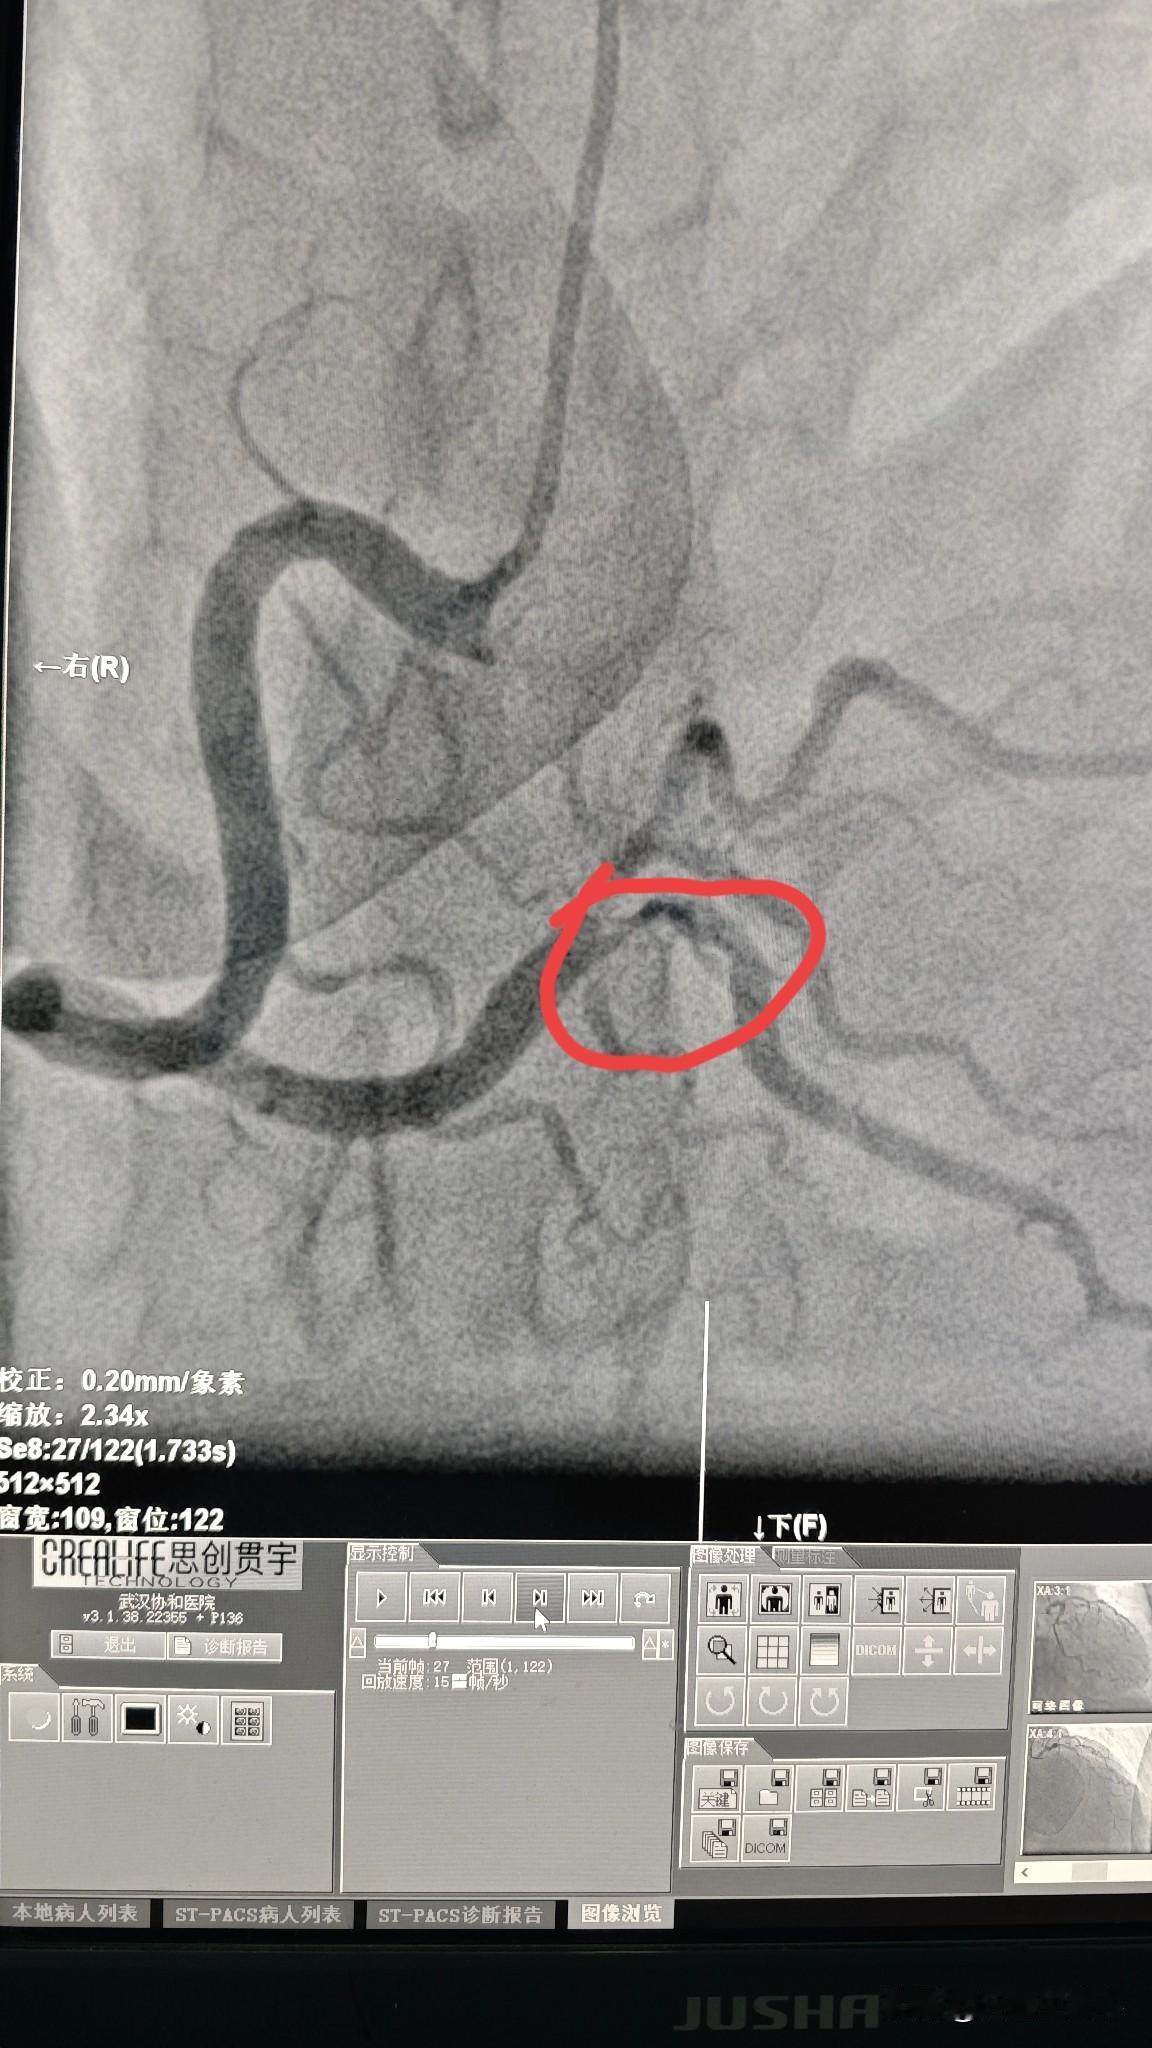

38 岁男性冠状动脉三支病变!38 岁男性患者,有高血压、糖尿病,近期还突发脑梗,老年病都全乎了。经过一段时间治疗,病情逐渐平稳。因心电图显示心肌缺血,考虑到全身多个器官的血管都有动脉硬化,就做了冠脉造影检查,结果显示三支病变(前降支、回旋支、右冠状动脉)。 在急性脑梗期间做冠脉支架风险较高,药物治疗了6个月后,先做了右冠状动脉,造影显示粗大的右冠状动脉远端有重度狭窄,做了一个支架后,血流恢复通畅。 前降支和回旋支的狭窄留作后续治疗,让患者先休养一段时间再说。年轻并不是不会得心脑血管疾病,而是需要更加注意平常生活。 如果有心脑血管疾病的家族史,在年轻时候就要注意体检查血糖、血脂、血压和动脉硬化的情况,饮食方面也要注意低盐低脂饮食,不吸烟,控制好这些危险因素,就能少患上这些慢性病。 如果已经出现了血压、血糖、血脂问题,尽早发现尽早干预和治疗,避免发展到冠心病阶段。